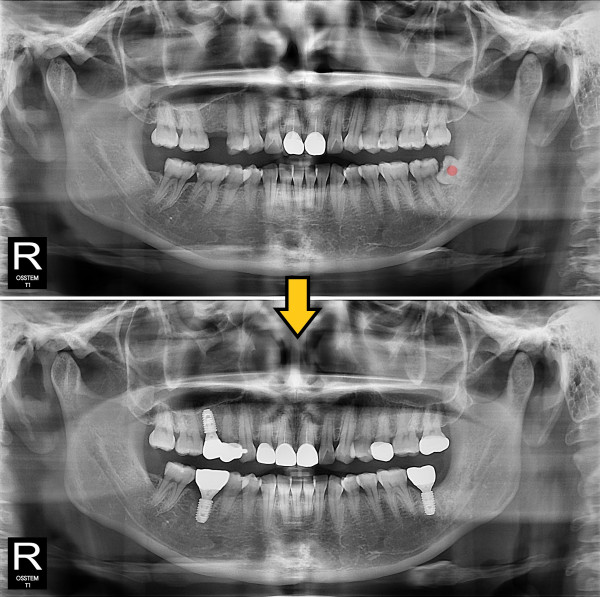

사랑니발치 부분 매복 사랑니

ae27575af29d49719312fde5a1f0cca6_1764402680_8006.jpg